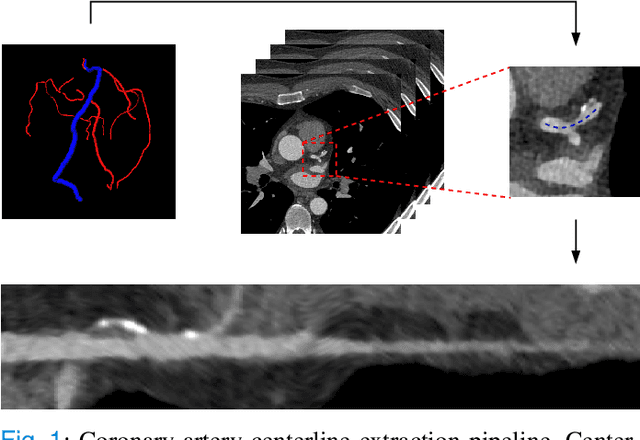

Abstract:Coronary CT angiography (CCTA) and intravascular ultrasound (IVUS) provide complementary information for coronary artery disease assessment, making their registration valuable for comprehensive analysis. However, existing registration methods require manual interaction or extensive segmentations, limiting their practical application. In this work, we present a fully automatic framework for CCTA-IVUS registration using deep learning-based feature detection and a differentiable image registration module. Our approach leverages a convolutional neural network trained to identify key anatomical features from polar-transformed multiplanar reformatted CCTA or IVUS data. These detected anatomical featuers subsequently guide a differentiable registration module to optimize transformation parameters of an automatically extracted coronary artery centerline. The method does not require landmark selection or segmentations as input, while accounting for the presence of IVUS guidewire artifacts. Evaluated on 48 clinical cases with reference CCTA centerlines corresponding to IVUS pullback, our method achieved successful registration in 83.3\% of cases, with a median centerline overlap F$_1$-score of 0.982 and median cosine similarities of 0.940 and 0.944 for cross-sectional plane orientation. Our results demonstrate that automatically detected anatomical features can be leveraged for accurate registration. The fully automatic nature of the approach represents a significant step toward streamlined multimodal coronary analysis, potentially facilitating large-scale studies of coronary plaque characteristics across modalities.